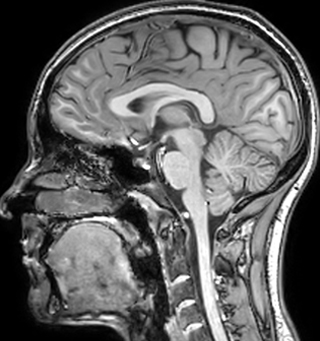

T1 - weighted

Myelin water imaging - T1 weighted

Myelin water imaging (echo 1)

Myelin water imaging with SENSE

Myelin water imaging with Compressed SENSE

With SENSE

With Compressed SENSE

Acquired resolution:

1 x 2 x 5 mm3

1.5 x 2 x 3 mm3

Number of echoes:

32 or 48

56

Echo spacing:

10 ms or 8 ms

7 ms

T1 - Weighted, Myelin Water Fraction Superimposed

MWI Spinal cord coverage

Spinal cord coverage

MWI Smaller, more isotropic voxels

Smaller, more isotropic voxels

MWI Excellent detail in quantitative maps

Excellent detail in quantitative maps

Images courtesy of Adam Dvorak, Department of Physics and Astronomy, University of British Columbia

20%

Myelin water fraction

0%